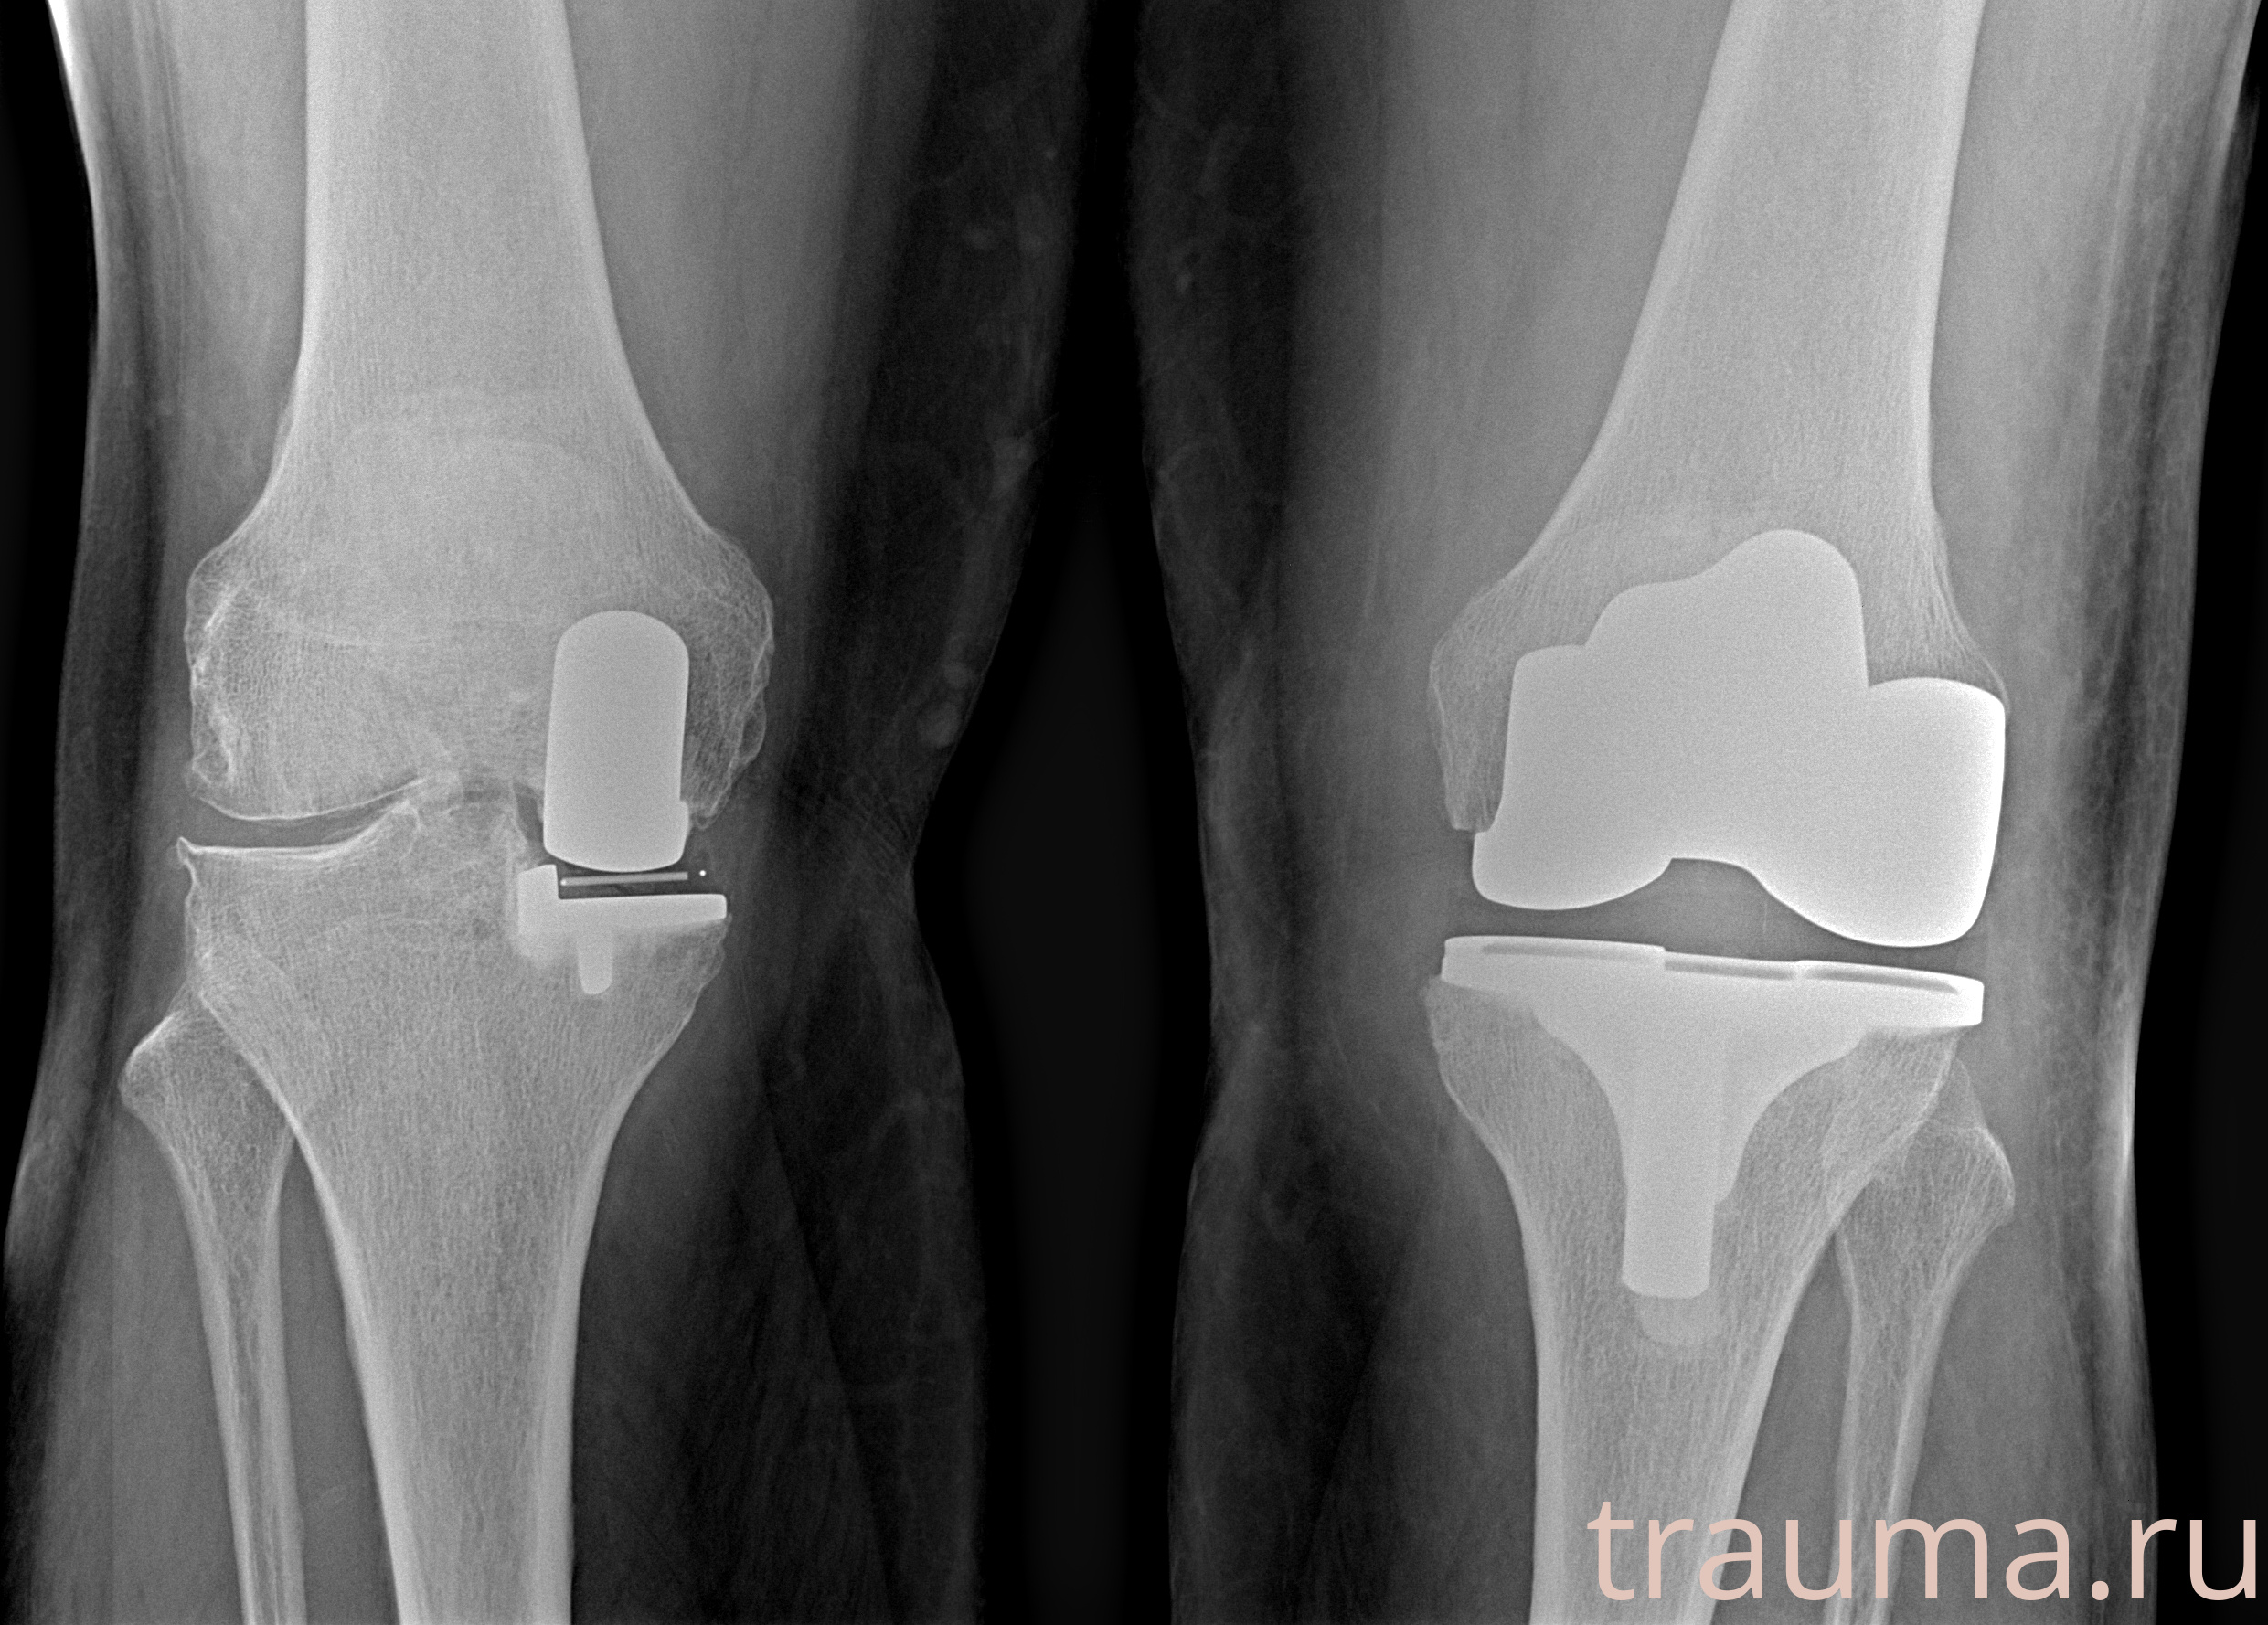

Правый

Рентгенограммы

МосРентген Центр

Левый